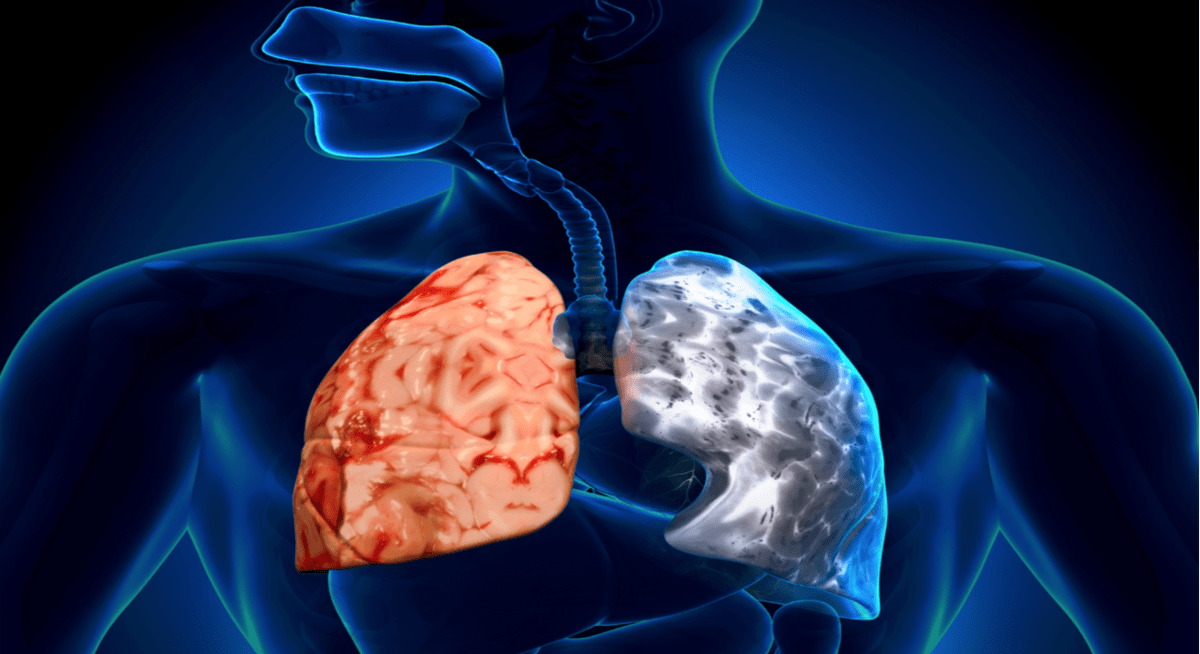

Η ΧΑΠ είναι μια φλεγμονώδης πάθηση που χαρακτηρίζεται από συμπτώματα όπως η δύσπνοια, ο βήχας, η παραγωγή φλέγματος και ο αναπνευστικός συριγμός και συνδέεται, μεταξύ άλλων, με αυξημένο κίνδυνο καρκίνου στους πνεύμονες.